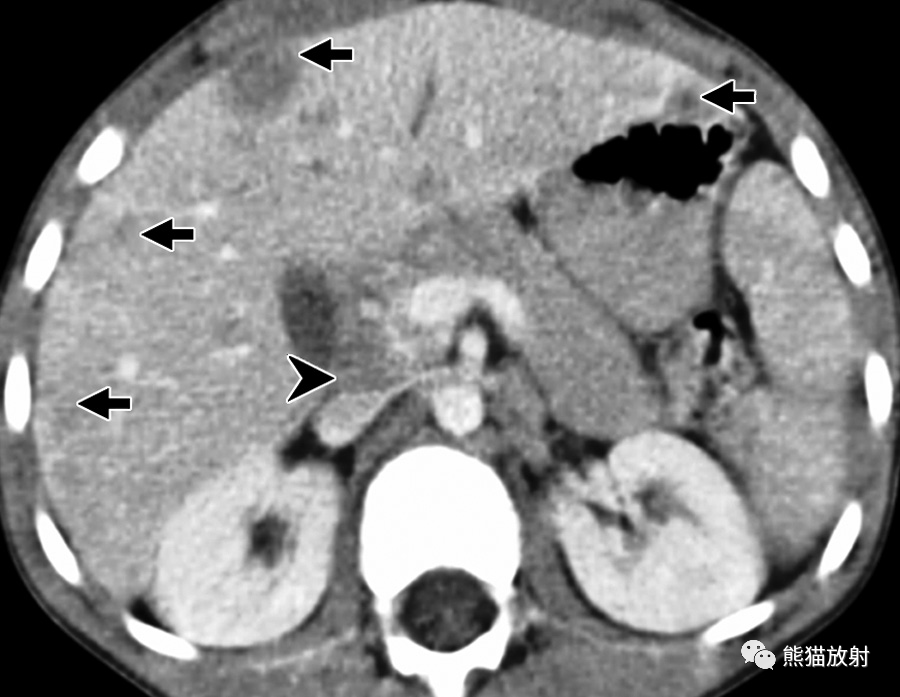

32岁 HIV/AIDS男性患者,细菌性紫癜,表现为发热。

(a)T1WI同相位图像显示肝右叶后段边界不清的等至轻度低信号结节(箭)。(b)脂肪饱和T2WI显示结节呈中高信号(箭),后方肝被膜下见数个较小结节(箭头)。(c)增强动脉早期图像显示结节周围不规则明显强化。(d)增强延迟期结节内部延迟强化,由于造影剂滞留在病灶内扩张的肝窦内,因此达到与周围肝静脉结构相似的信号强度。